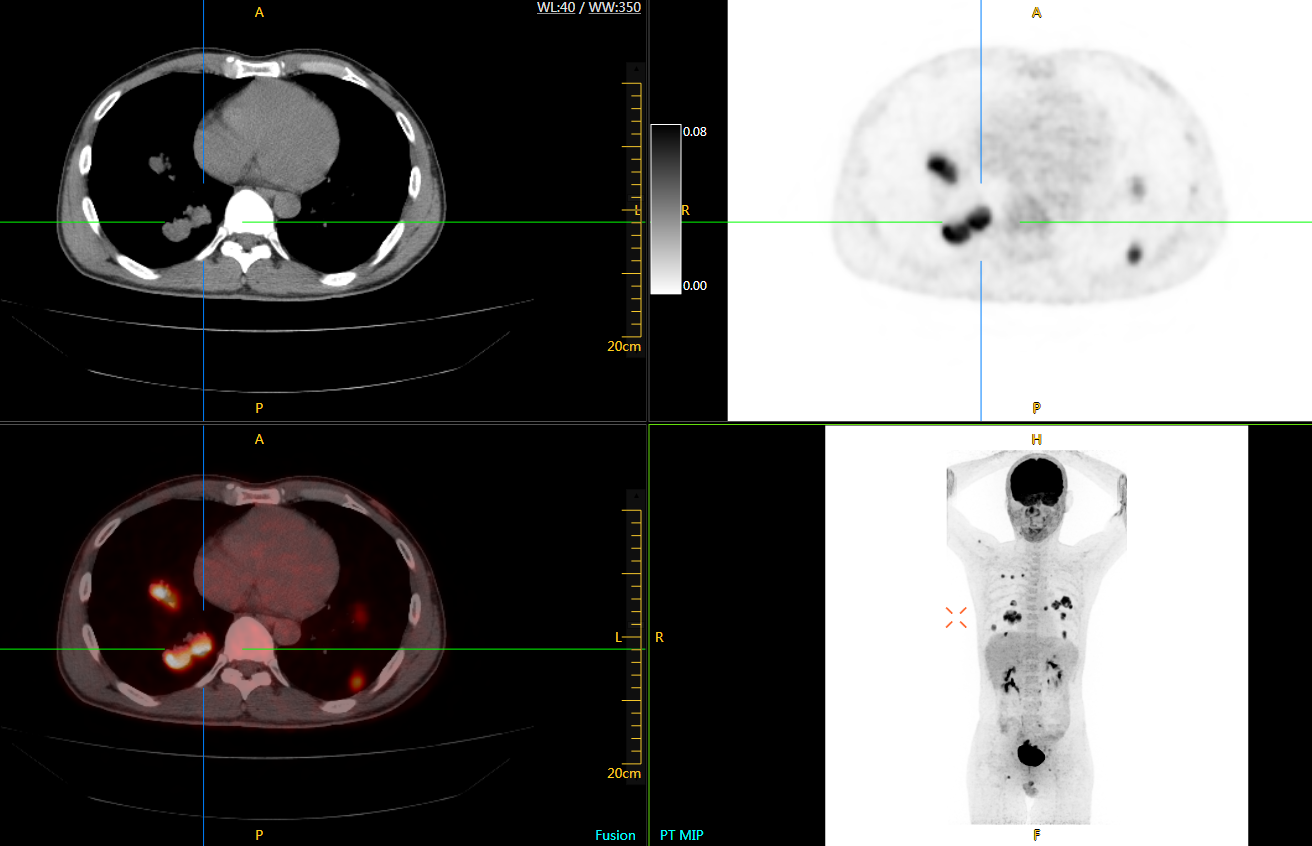

圖例

直腸癌

男,45歲,直腸癌術(shù)后9個(gè)月,發(fā)現(xiàn)肺占位

臨床診斷:直腸區(qū)術(shù)后改變,復(fù)發(fā)伴骶骨受累,雙肺多發(fā)轉(zhuǎn)移